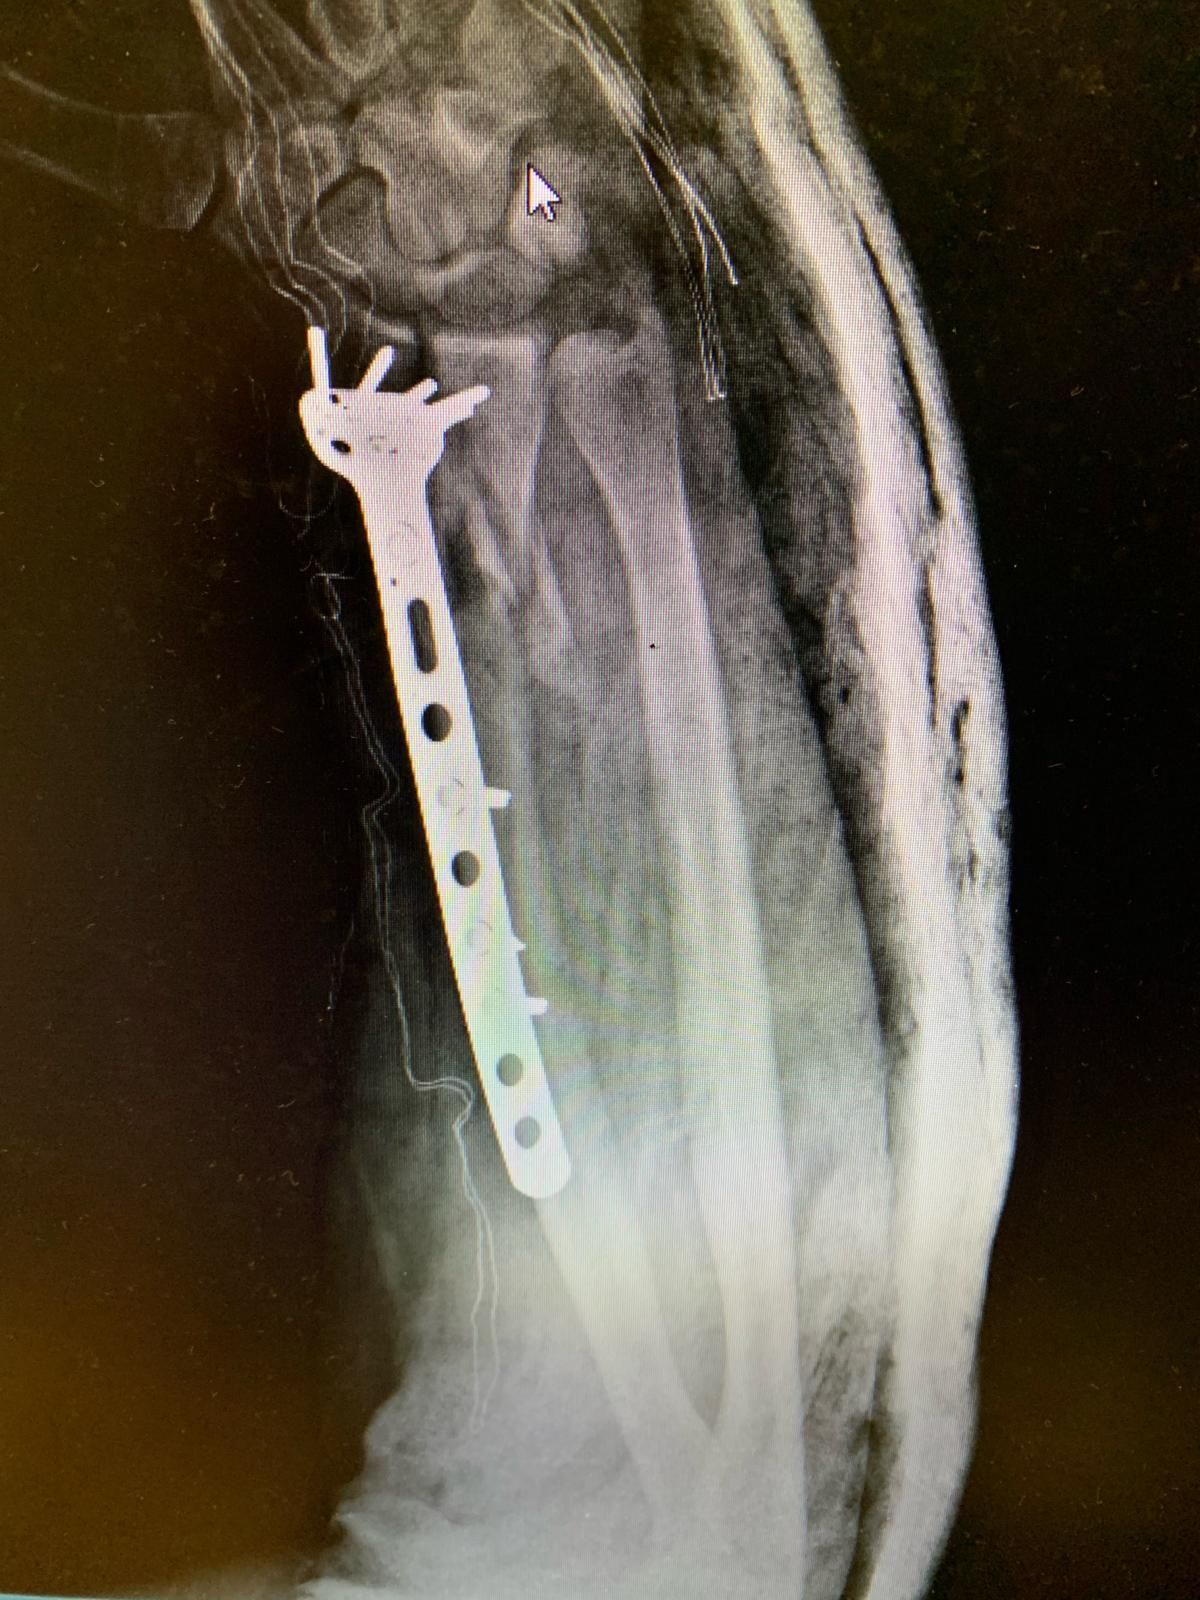

Traumatologia adulta e pediatrica

La traumatologia rappresenta un ambito fondamentale dell’attività specialistica, rivestendo un ruolo cruciale nella cura e nella riabilitazione dei pazienti colpiti da eventi traumatici. La gestione delle

lesioni traumatiche dell’apparato muscolo-scheletrico si estende a una vasta gamma di condizioni, che comprendono traumi articolari, fratture di varia gravità e lesioni che interessano sia gli arti superiori che quelli inferiori. Grazie a un’esperienza ospedaliera consolidata, i professionisti sono in grado di affrontare non solo le urgenze traumatiche, che richiedono un intervento rapido e preciso, ma anche la gestione degli esiti post-traumatici, ponendo particolare attenzione al recupero funzionale e al miglioramento della qualità della vita dei pazienti. L'approccio multidisciplinare e l'uso di tecnologie avanzate sono cruciali per garantire risultati ottimali.